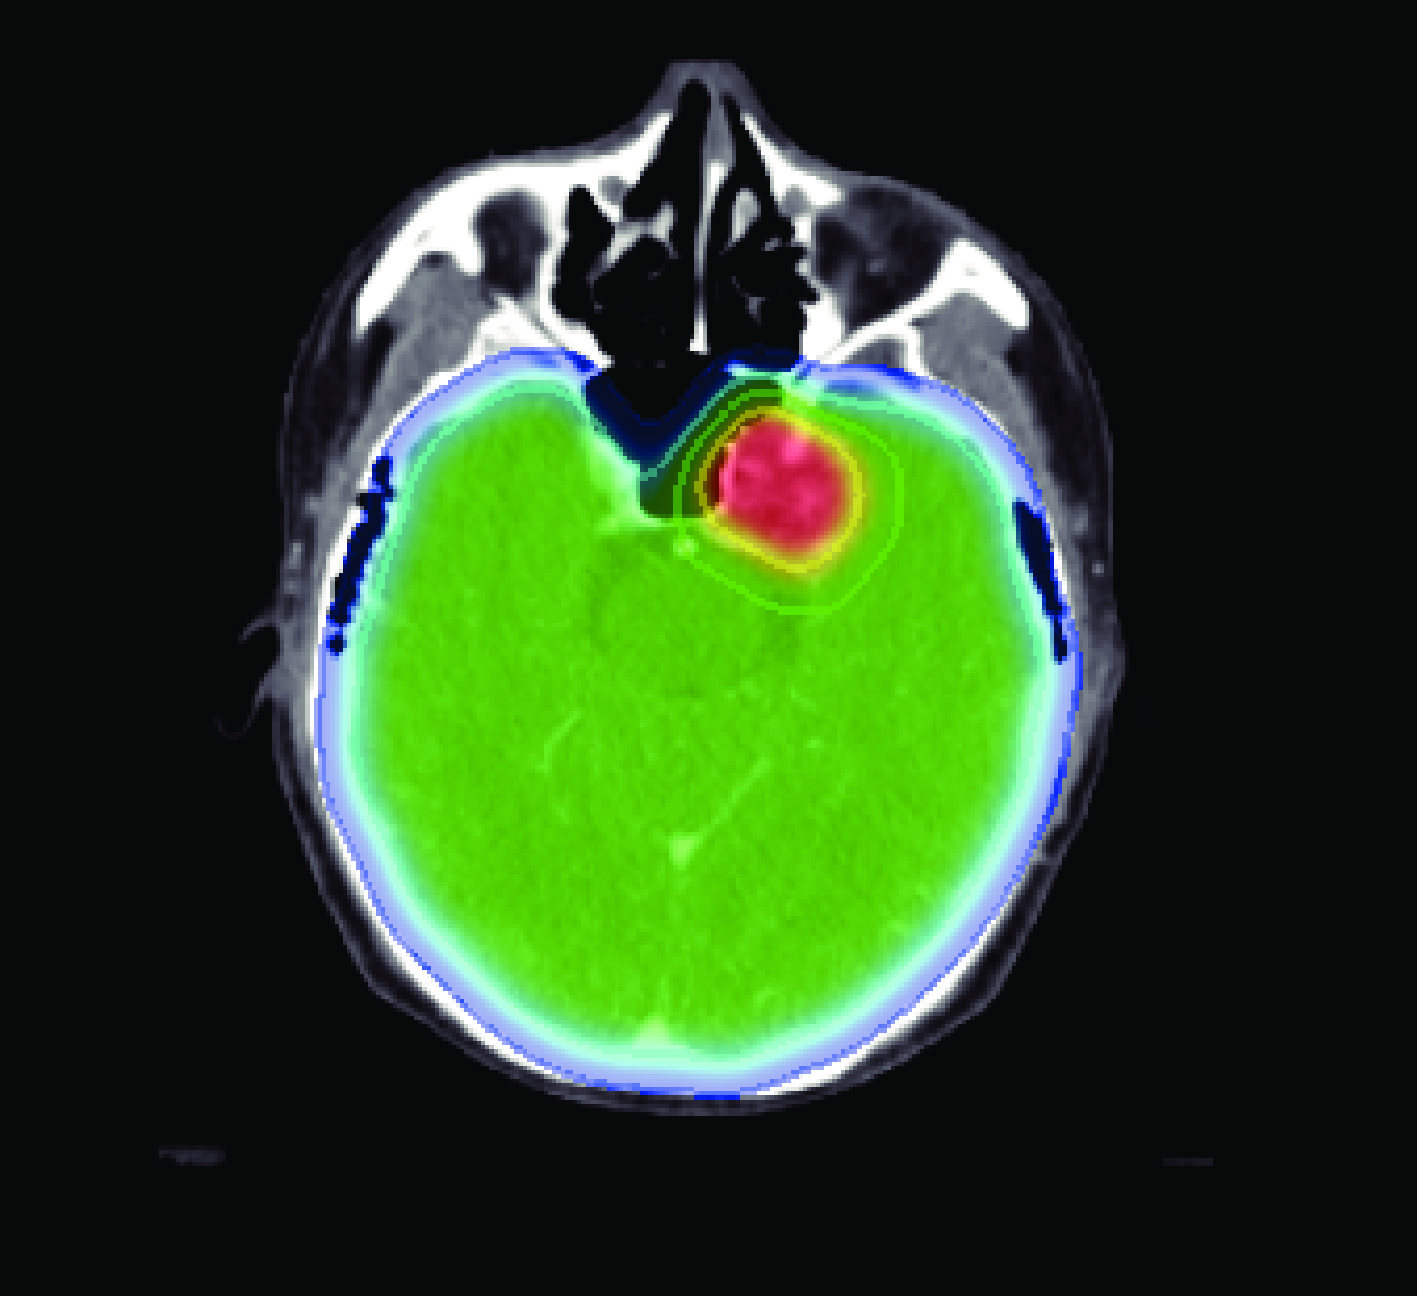

Within the medical-image platform MeVisLab, we complete DICOM registration, target delineation, and RTStruct/RTDose interfaces; the open-source Monte Carlo code OpenMC is used as the engine to execute neutron-transport simulation, realizing HU-to-material mapping and variable-mesh calculation.

Validation with clinical CT data simulated by the system shows that at a depth of 22 cm in the tumour target, the boron dose accounts for 80.9% of the total dose.